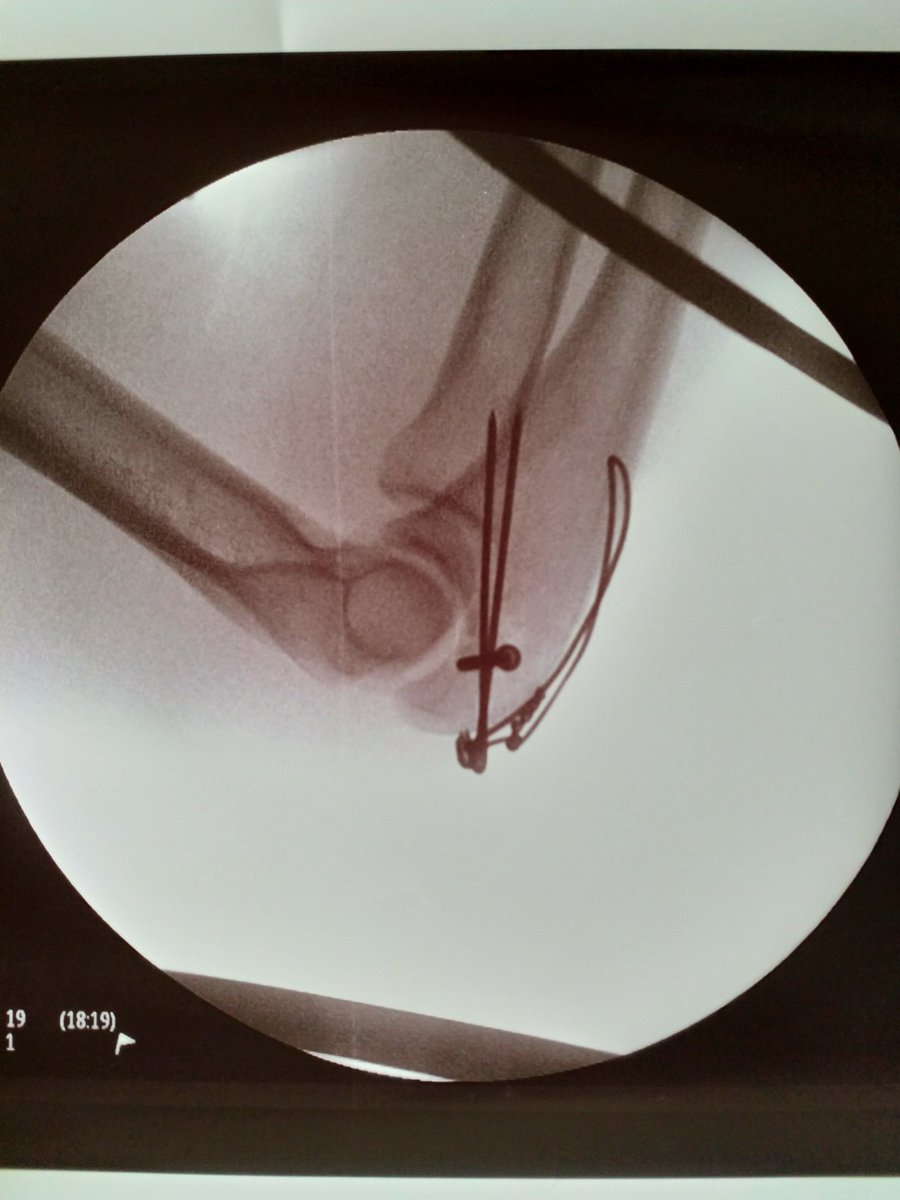

骨折から3か月経ちました。 今週にレース復帰となりました。 僕にとって新たなシーズンの始まりです。 美和ちゃん始めサポートしてくれた皆様に感謝です。ありがとうございます🙇 怪我してからも皆さんのメッセージがとても力になりました💪💪ありがとうございました。 これからも頑張ります!!

肘の骨折から20日。 自転車の上に戻って来ました。 これ以上嬉しい事はないね。 ここからの景色が見たかった。 20 jours après le retour au vélo. Je suis content.✌️

たくさんのメッセージありがとうございます。 3月13日落車で肘を骨折してしまいました。 歩行に問題があった為に日本にて精密検査を行った結果。 骨盤骨折と診断されました。 が手術は必要ありません。 肘のリハビリもしながら、骨盤も労りながら また、皆さんの前にまた復帰出来るように頑張ります。